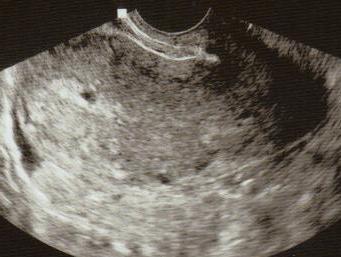

voltam ma uh-on ...és a baba jól van 19 mm-es és már ugrándozott!!!!!!!!!

de sajna üröm az örömben hogy van egy jó 3 cm-es vérömleny mellette....holnaptól szedek gyyógyszert rá ami segítí elméletileg hogy eltünnyön a vérömleny........

2 hét mulva megint megyek uh-ra.........